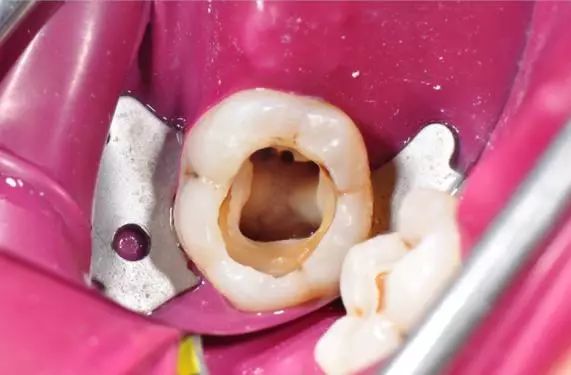

通常嚟講,牙醫唔會輕易拔牙嘅!即使你牙齒痛得非常厲害,都要睇下你蛀牙嘅程度!一般嚟講,輕度蛀牙無傷到牙神經,牙醫會用樹脂填充來補牙。如果要抽牙神經,咁就係話明你嚴重蛀牙,需要進行根管治療同埋戴個牙套保護。

如果需要進行根管治療、紅外線治療器輔助治療的話,價錢係喺1500蚊左右。